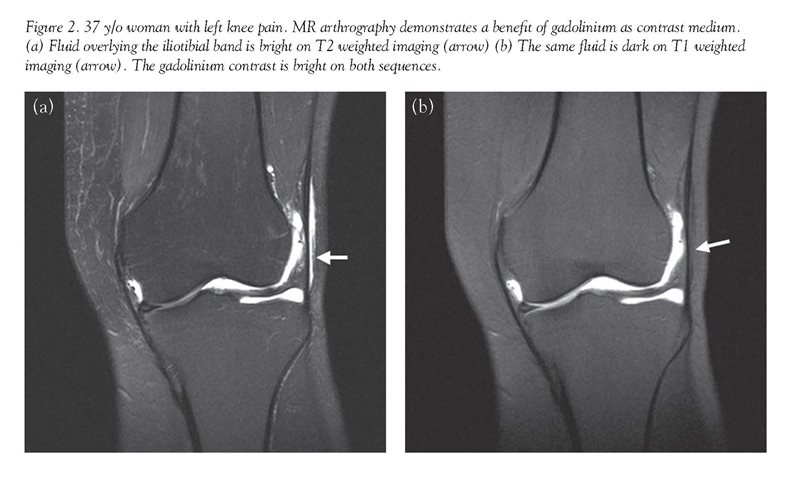

MR arthrography can be performed using sterile saline or gadolinium as a contrast medium, but gadolinium offers several advantages because of its paramagnetic properties. (This term refers to a characteristic of certain substances that locally alters the magnetic field in tissue and provides greater signal intensity for MR imaging.) Gadolinium's paramagnetic properties allow contrast material to become bright on both T1 and T2 weighted imaging under correct dilution. (The amount of gadolinium contrast needed is very small—ideally a dilution of 1:250.) This characteristic of gadolinium allows visualization of contrast as it distends joint recesses and outlines intra-articular structures and potential abnormalities. Though saline contrast also distends the joint capsule, it is only bright on T2 weighted imaging, and is indistinguishable from other fluid commonly found around joints, such as bursal fluid [Fig. 2]. Fat suppression is particularly critical in MR arthrography because of the similar signal of gadolinium contrast and normal fat. The need for fat suppression in turn requires the use of high field-strength magnets.